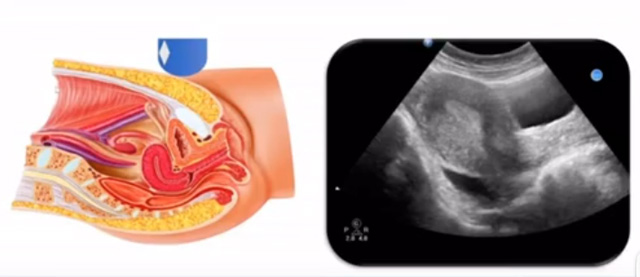

女性生殖係統包括內、外生殖器官及其相關組織以及鄰近器官,其中內生殖器是秋葵视频男人的加油站超聲檢查的主要對象。那麽內生殖器包括陰道、子宮還有輸卵管及卵巢。輸卵管及卵巢稱為子宮附件。子宮是倒置梨形,但是它是空腔厚壁肌性器官。它的正常值在育齡婦女。超聲探頭放在貼近腹壁盆腔上麵位置,來看這個子宮在超聲上麵的表現。從輪廓上來講,和示意圖是一樣的。這就是在超聲上麵顯示的一個子宮的圖片。子宮在不同的時期與子宮頸的比例。成年婦女指的是育齡婦女為2:1子宮體是比較大的,嬰兒期為1:2說明宮頸比較大,絕經期1:1。所以秋葵视频男人的加油站在看到子宮圖時候可以根據宮體宮頸比例大致可以推測屬於哪個時期的婦女。另外還可以根據比例大小來推斷是一個正常子宮還是異常子宮。

子宮從外到內,漿膜層、肌層、粘膜層。宮體部宮頸為梭形結構。宮腔為上寬下窄的三角形,連接為峽部。子宮有什麽功能呢?月經血產生跟排出通道,精子運行通道受精作用。囊胚著床及胎兒發育、生長的場所。分娩時產生宮縮使胎兒、胎盤娩出。未孕的子宮是很小的,已孕子宮就非常大,平均胎兒都有6斤重。所以這個後壁就體現出來。輸卵管由子宮角部向外延伸,為一對細長而彎曲的管道,呈管狀中空結構,大概長度是8-14厘米,粗1-4毫米,它的下方為卵巢和闊韌帶。間質部是厚一點的,峽部是比較窄的地方,壺腹部,漏鬥部。正常情況下,輸卵管在普通超聲DR難以顯示。